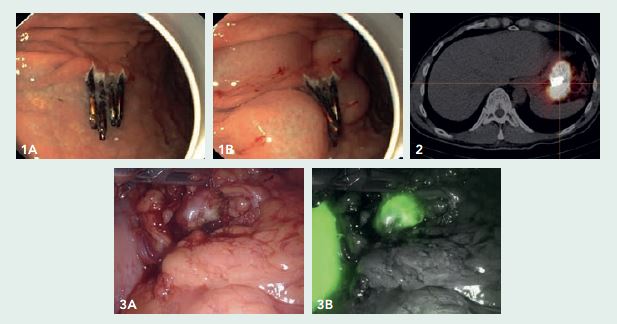

Een gastroscopie in ons centrum toonde geen aanwijzingen voor een lokale resttumor of synchrone afwijkingen elders in de maag. Het ESD-litteken met clips (figuur 1A en 1B) bevond zich aan de grote curvatuur, 6 cm distaal van de cardia. Bij EUS waren er geen verdachte lymfeklieren.

In ons centrum werd in het multidisciplinaire overleg besloten om een robot-geassisteerde sentinel node-procedure uit te voeren. Mocht de sentinel node negatief zijn, dan zou er alleen een regionale lymfeklierdissectie (in het bijbehorende arteriële stroomgebied) worden uitgevoerd. Mocht de sentinel node positief zijn, dan zou er een gastrectomie met D2 lymfadenectomie worden verricht. De dag voor de operatie onderging de patiënt een gastroscopie waarbij een ‘dual-tracer’, bestaande uit Technetium-99m en Indocyanine-groen, in 4 kwadranten om het oude ESD-litteken werd ingespoten (figuur 1A en B). Na 15 minuten en na 2 uur werd er een scintigrafie gemaakt. Hierop kon geen sentinel node worden geïdentificeerd (figuur 2), alleen het injectiegebied lichtte op.

De dag erna onderging de patiënt een robot-geassisteerde sentinel node-procedure, waarbij met de ‘Firefly’-camera en een gamma-probe 5 groene en ‘hete’ lymfeklieren werden gevonden. Vriescoupes toonde de aanwezigheid van metastase in één vergrote, bolronde lymfeklier (figuur 3A-B). Deze lymfeklier bevond zich ter plaatse van de distale arteria lienalis (lymfeklierstation 11d). Aansluitend werd een resectie verricht. Met behulp van ICG-fluorescentie kon het oude ESD-litteken mooi gevisualiseerd worden en lukte het om een partiële (in plaats van totale) maagresectie uit te voeren. In het gastrectomiepreparaat werd geen resttumor aangetoond en alle 32 niet-sentinel nodes waren negatief voor maligniteit.